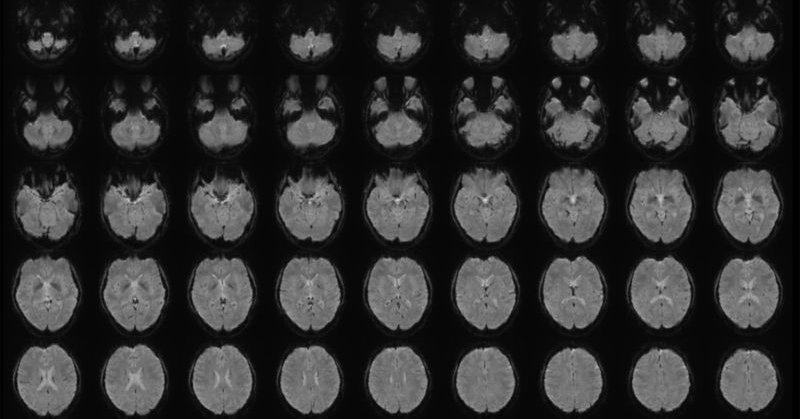

【すごい】NTT、頭の中で「思い浮かべたこと」をAIでテキスト化する技術公開 https://t.co/L4NyEtx3sB 映像を見ているとき、あるいは過去に視聴した映像を思い浮かべた時の脳の状態を、脳の活動部位を特定できる「fMRI」で計測。どのような映像を見て、思い浮かべたのかをテキストで出力するという。

ヒトが知覚・想像している映像の内容を説明するテキストを,脳活動から生成するデコーディング研究のpreprintが公開されました. fMRIで計測した脳活動から解読した意味特徴をもとに,テキストの繰り返し最適化を行うことで,脳に表現されている意味情報を捉えたテキストを生成するという研究です.

We combined semantic feature decoding with a novel text optimization method assisted by a masked language modeling (MLM) model to iteratively optimize text. The generated text captured viewed content, achieving ~50% accuracy in identifying videos out of 100 (chance=1%).

While the semantic features were useful for predicting video-induced brain activity in the language network, intelligible descriptions were still generated even when this network was ablated, highlighting explicit representations of structured semantics outside this network.